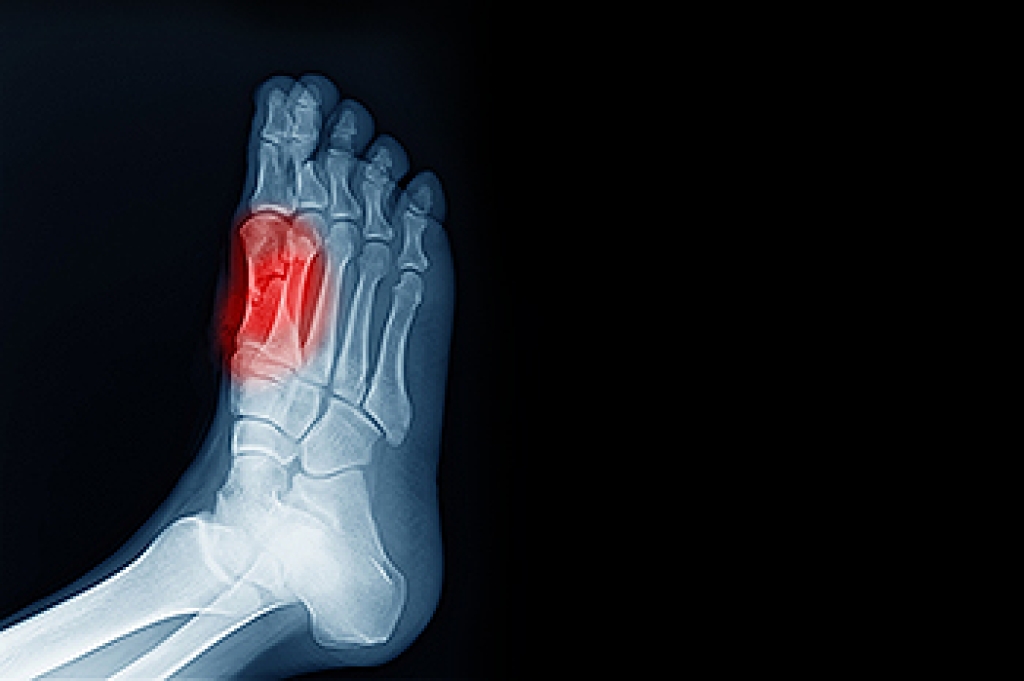

Big Toe Pain Caused by Sesamoiditis

Sesamoiditis is a painful condition involving two small bones located beneath the big toe joint. These sesamoid bones are embedded within a tendon that helps flex the big toe and absorb weight-bearing pressure. When repetitive stress or trauma affects this area, the surrounding tendon can become inflamed, causing pain beneath the ball of the foot. High-impact sports, foot injuries, poor foot mechanics, or shoes that lack adequate support can increase the risk of sesamoiditis. Symptoms include swelling, tenderness, and sharp pain when bearing weight or bending the big toe. This often builds gradually and may make walking or running difficult. A podiatrist can diagnose sesamoiditis by examining the foot, checking for tenderness, and ordering imaging tests to rule out fractures or other problems. In severe cases, surgery may be recommended to remove or repair the affected bone. If you have this type of pain in the big toe, it is suggested that you schedule an appointment with a podiatrist for an exam and appropriate treatment options.

Sesamoiditis is a condition of the foot that affects the ball of the foot. It is more common in younger people than it is in older people. It can also occur with people who have begun a new exercise program, since their bodies are adjusting to the new physical regimen. Pain may also be caused by the inflammation of tendons surrounding the bones. It is important to seek treatment in its early stages because if you ignore the pain, this condition can lead to more serious problems such as severe irritation and bone fractures.